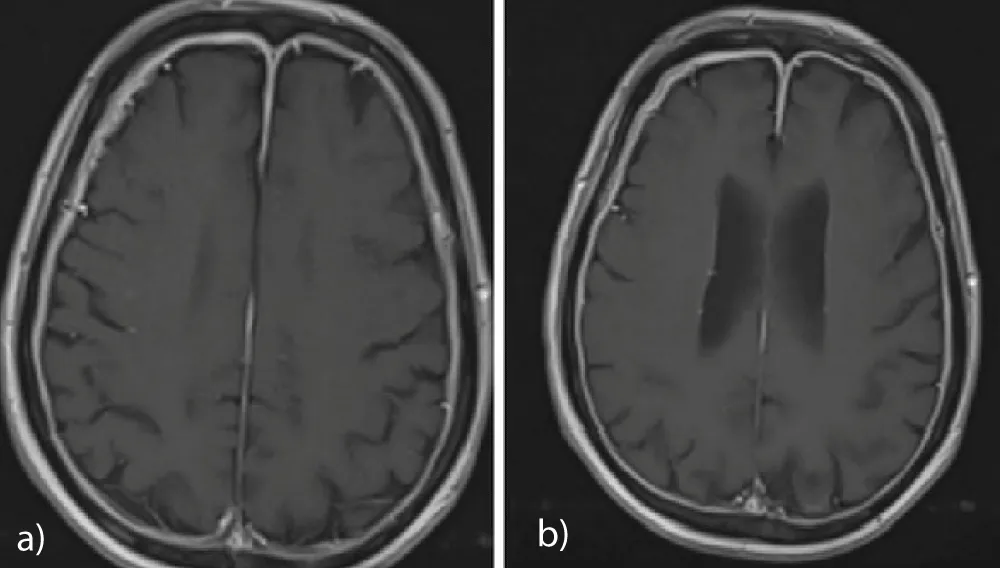

The patient was a 69-year-old man who had been treated with goserelin, abiraterone, and lutetium-177 due to metastatic prostate cancer with extensive bone involvement. He had been evaluated as having stable disease and was followed accordingly. His medical history included hypertension and aortic stenosis. The patient presented to the neurology outpatient clinic with complaints of headache and facial paralysis. Cranial MRI revealed diffuse thickening and contrast enhancement of all dural surfaces on T1-weighted images, and he was subsequently referred to our clinic (Figure 1a,b). On physical examination, his general condition was moderate; he was conscious, oriented, semi-cooperative, and bed-mobile, with a Glasgow Coma Score of 14-15. Neurological examination revealed bilateral muscle strength of 4+/5 and left-sided facial paralysis. Anti-edema treatment with dexamethasone was initiated. Whole-brain radiotherapy was delivered using a LINAC device with 6 MV photon energy at a dose of 8 Gy in a single palliative fraction. Three weeks after radiotherapy, the patient was reported to have died due to pneumonia.

Figure 1: a,b: Diffuse dural thickening and contrast enhancement on T1-weighted cranial MRI.